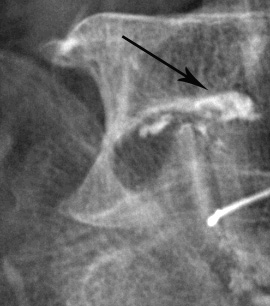

Radiographie de l'épaule. L'épaule a 2 articulations : l'articulation acromio-claviculaire (flèche pleine) et l'articulation omo-humérale (flèche creuse).

Infiltration de l'articulation acromio-claviculaire (épaule).